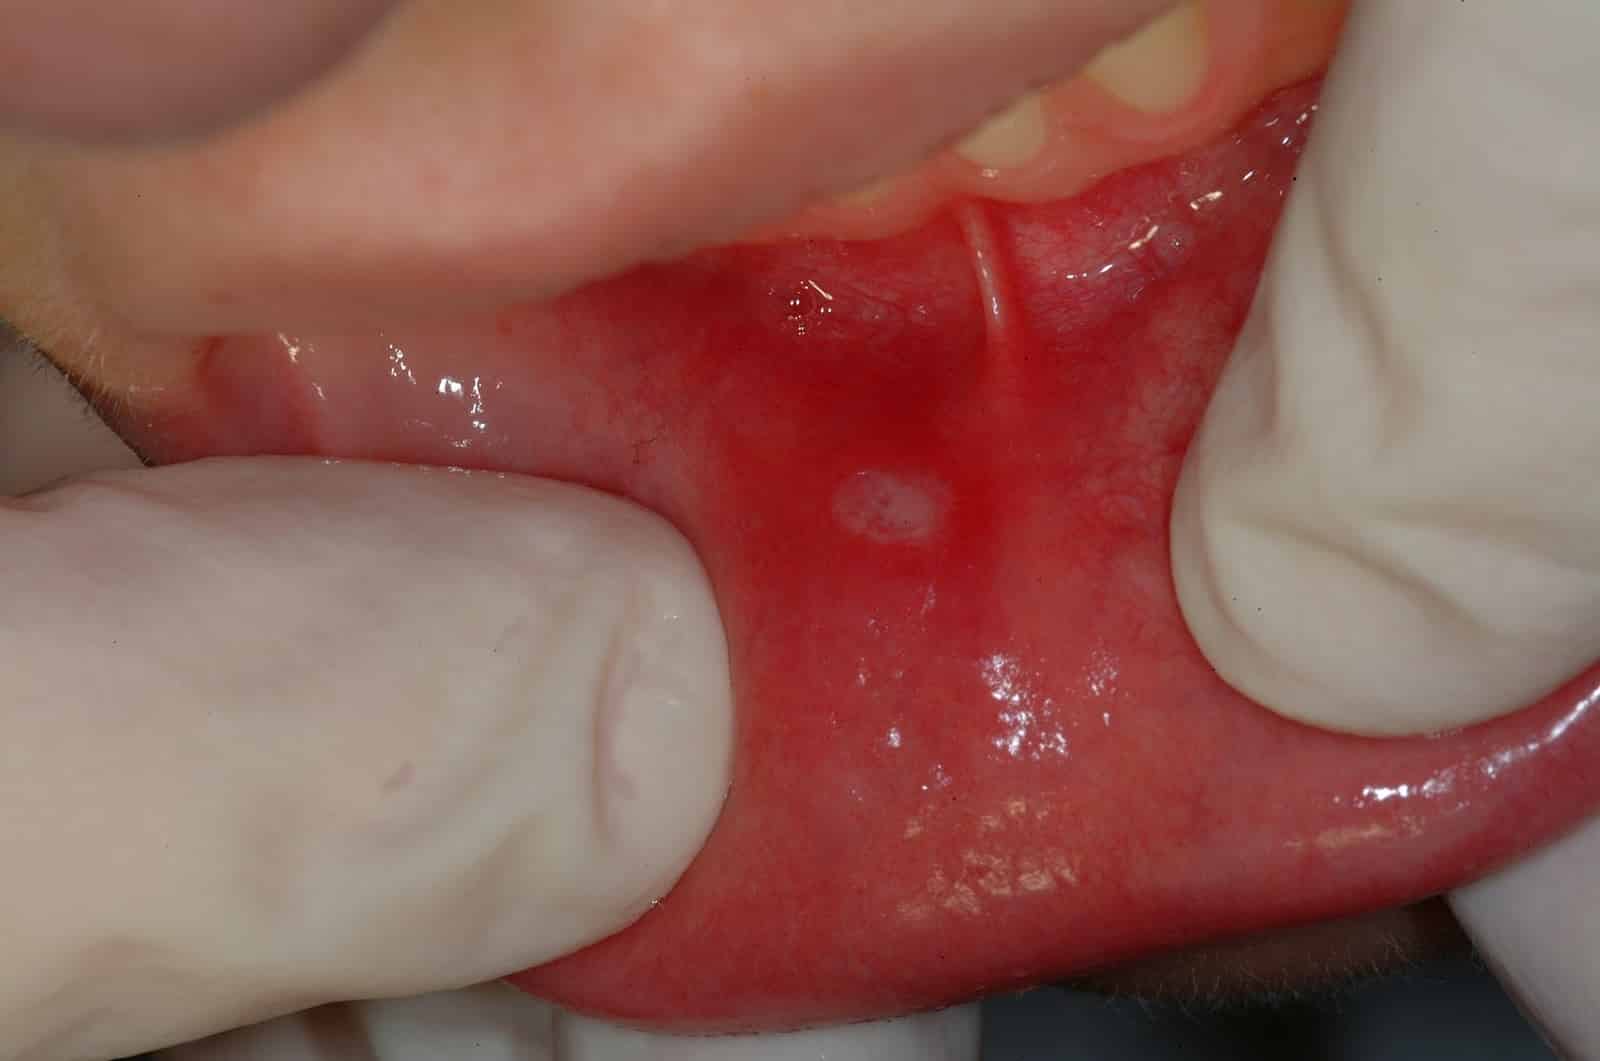

Афтозный стоматит у детей

Фото афтозного стоматита у ребенка

При этом недуге всегда растет температура, а во рту возникают характерные язвочки с четким алым ободком – афты. Афтозный стоматит у ребенка легко опознать с помощью фото, заглянув на соответствующий медицинский форум.